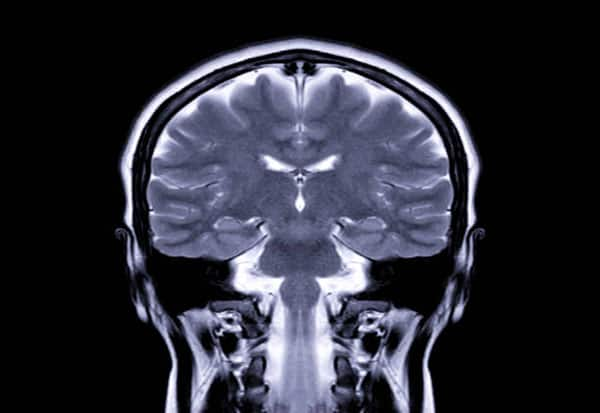

New Delhi: A new study shows that processing numbers could be happening in a region deep within the brain indicating that humans might have acquired the ability early during evolution.

As the patients responded, the team observed activity happening in the putamen -- a part of the cerebrum and located deep within the brain.

The putamen is usually related to functions such as movement and cognition, but rarely to higher-level aspects of human intelligence like solving calculus, the researchers explained.

Consciousness and abstract thought are typically attributed to the cerebral cortex (part of the cerebrum), which evolved later in human evolution and forms the brain's outer layer, they added.